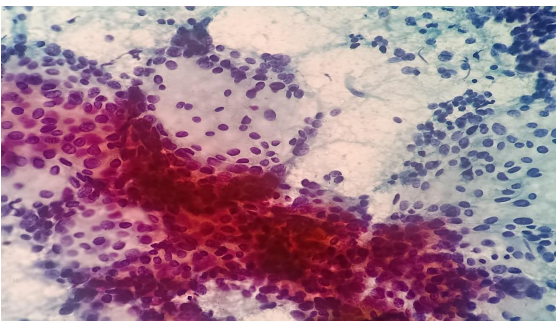

A 38 year old female presented with the complaints of pain and difficulty during swallowing and history of weight loss. Up on examination, a swelling was noted on the left side of her neck, which moved with deglutition. Ultrasound (USG) revealed a well circumscribed hypoechoic nodule measuring 3.2x2.1cm in the left lobe of thyroid with no extrathyroidal extension, however the nodule was compressing the esophagus. Fine needle aspiration was performed on the lesion and stained with Papanicolaou (PAP) stain and May Grunwald Geimsa (MGG) stains. The smears exhibited high cellularity with globoid clusters and three dimensional tissue fragments composed of aggregates of cells with central core of homogenous basement membrane material with cells having basaloid morphology and scant cytoplasm (Figure 2). MGG smears highlighted pink/ magenta amorphous basement membrane hyaline globules in the clusters of tumor cells (Figure 3). Cell block preparation of fine needle aspiration showed cribriform pattern of tumor cells with hyaline globules (Figure 4). Immunocytochemistry conducted on cell block shows TTF-1 positivity in normal thyroid follicles and negative staining in tumor cell clusters. CD117 and synaptophysin were inconclusive on cell block, but based on morphology this case was reported as adenoid cystic carcinoma of thyroid. Contrast-enhanced computed tomography (CECT) prior to surgery depicted a well defined heterogeneously enhancing hypodense lesion in the left lobe of thyroid measuring 3.2x2.1x1.7cm with no  additional lesions or abnormalities noted in the adjacent structures like trachea, larynx, oesophagus or upper mediastinum(Figure 1).  The excised left hemi-thyroidectomy specimen was received which showed a grey white solid homogenous lesion measuring 3.5x2.2x2cm reaching till the capsule. No cystic spaces/papillary projections/colloid seen in the lesion grossly. Adjacent thyroid parenchyma was normal. Histopathology sections showed tumor arranged in tubules and cribriform pattern along with hyaline globules suggesting the diagnosis of adenoid cystic carcinoma of thyroid, limited to thyroid without extra thyroid extension (Figure 5). IHC with CD117 showed cytoplasmic positivity in tumor cells further supporting the diagnosis (Figure 6).

Figure 4: H &E section from Cell block preparation of fine needle aspiration (20x) showing cribriform pattern of tumor cells with hyaline globules.